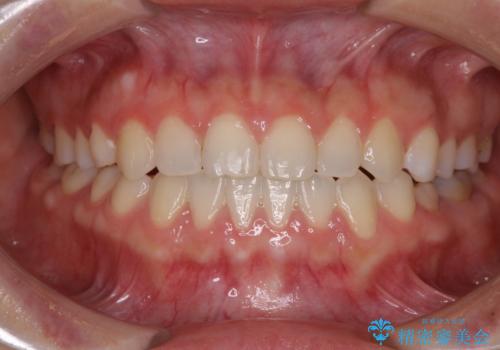

クロスバイト改善中には歯髄壊死を起こすリスクがあるため、神経に問題がないか確認しながら治療を進めて行く必要があります。

思っていたよりも早くクロスバイトは改善され、歯髄壊死に至ることなく、無事に治療を終えることができました。